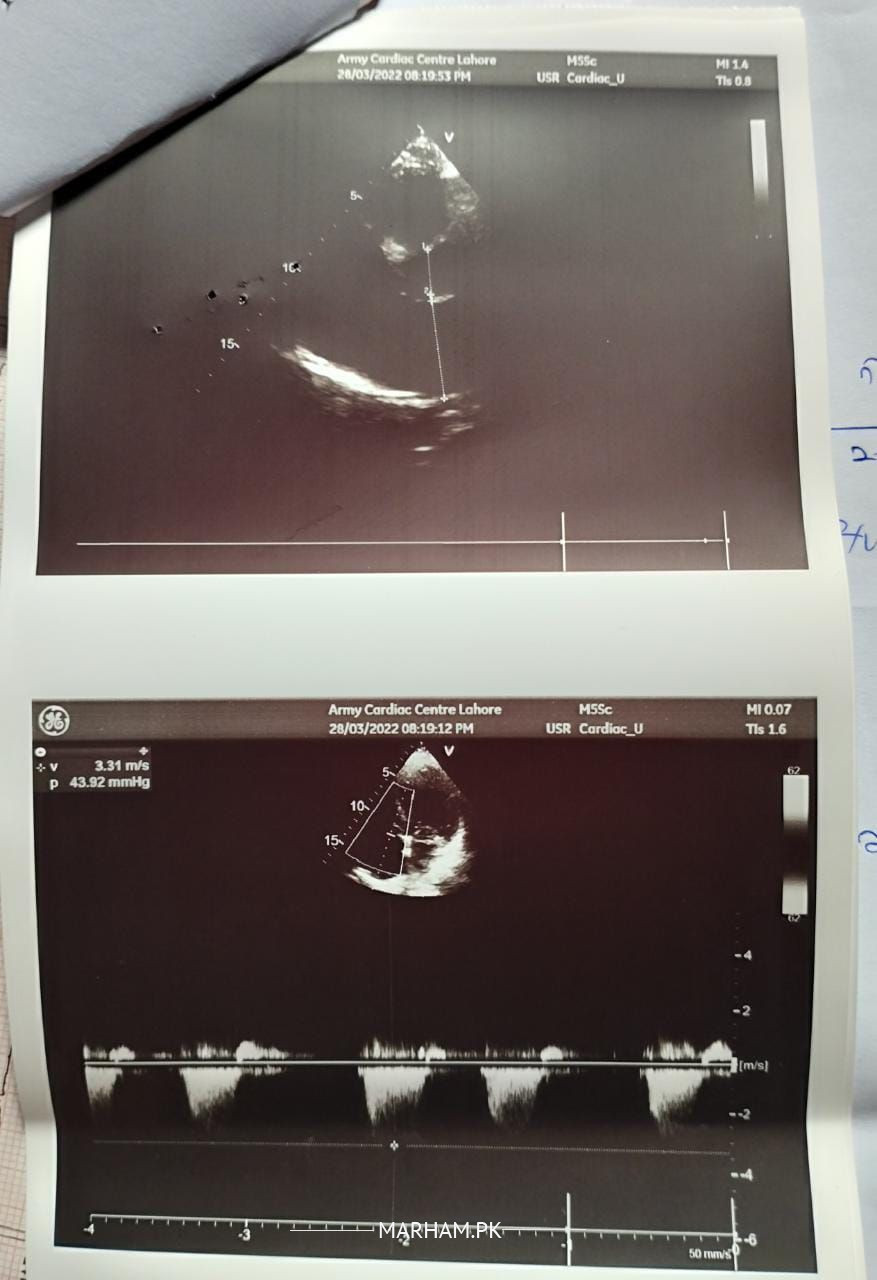

A.o.A! Please Check Reports And Answer Me How I Do My Uncle Have Heart Issue Doctor Says In Ka Heart Week Ho Gya Ha Only 20% Work Kar Raha Please Guide Karen Kya Karna Chaiye.

Yes, heart is weak and valves are leaky. please tell what medicines is he taking? had he ever had heart attack? angiography / plasty done? need detailed history sir

Im Upload Pic Of Medicines They Never Have Heart Problem 1st Time They Have Problem

This Medicine They Used Never Him Any Heart Issue 1st Time This Problem